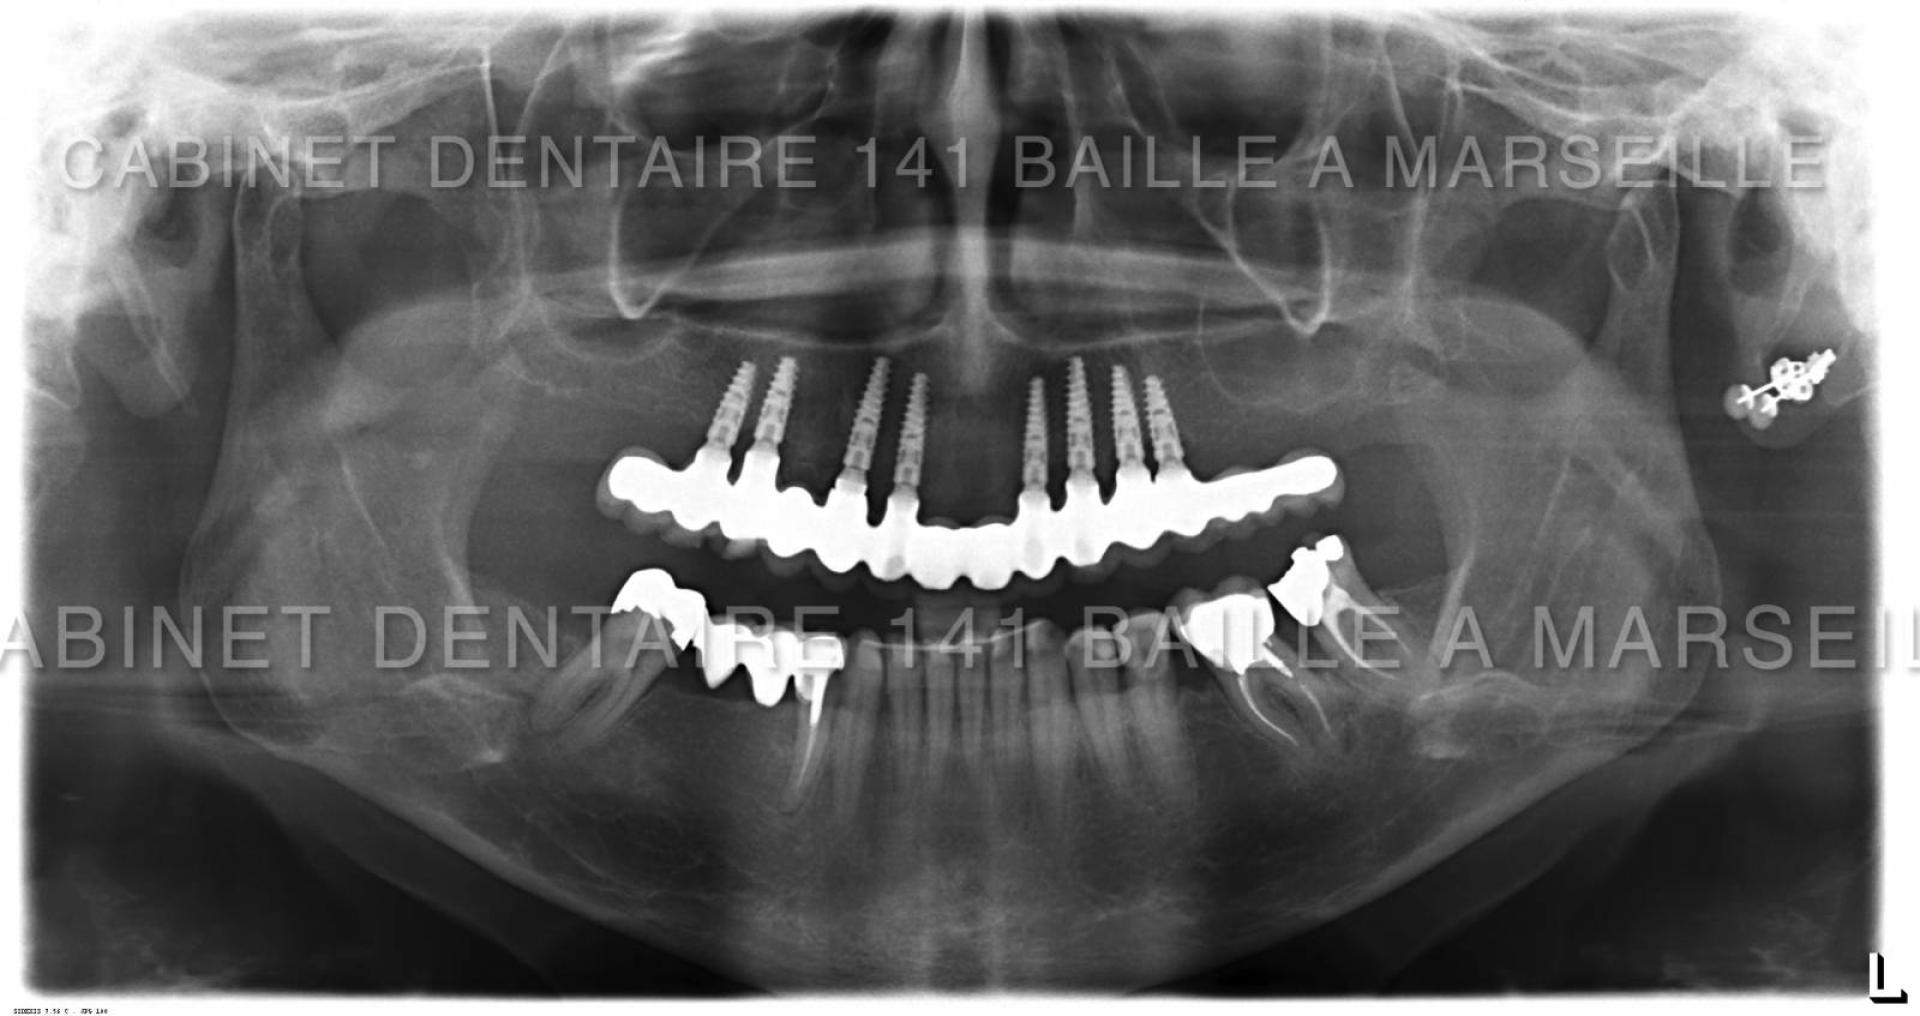

Il peut arriver qu'un patient soit obligé de remplacer toutes ses dents par des implants  dans certains cas de maladies de gencives très agressives qui entrainent une destruction de l'os support des dents .

Avant l'implantologie,ces patients n'avaient pas d'autres solutions que le port d'un appareil dentaire amovible aussi appelé par le grand public "dentier".Ces patients étaient amoindris psychologiquement car ils ressentaient le port de cette Prothèse comme un signe précoce de sénilité.De plus les appareils dentaires s'avéraient astreignants à l'usage .Ces appareils engendraient aussi un affaissement osseux rapide car l'os sous l'effet des pressions masticatoires se résorbait.

De nos jours il est possible pour ces patients d'avoir recours à des techniques implantaires appelées implantation complète en général effectuées dans la meme journée .On appelle cette technique la technique d'implantation complète avec mise en charge immédiate (MCI).

Ces techniques necessitent toutefois un chirurgien implantologiste qualifié et formé à ces techniques de mise en charge immédiate,d'un plateau technique complet avec bloc opératoire stérile ,prothésiste,et personnel d'assistance chirurgical qualifié.